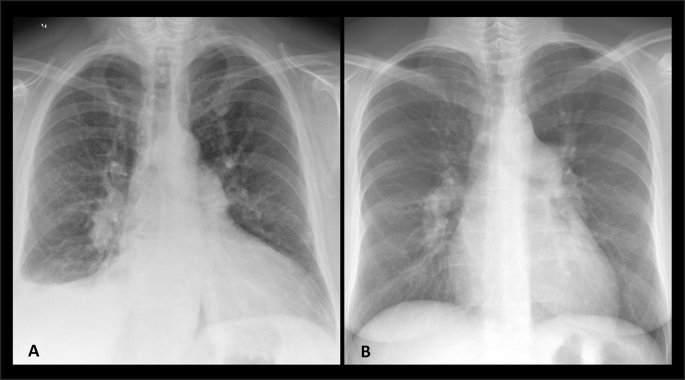

6–9: PVH-Stages (above) + CpcPH (with superimposed main & central pulmonary artery dilatation)56,57,76 [Fig. 6].

Frontal Chest X-Ray images from 2 Study Population subjects represent the PVPs of both forms of cardiopulmonary-derived Pre-Capillary PH, including: CpcPH: Main and central pulmonary artery dilatation superimposed on PVH (Stage 2-Late in this case) (A). Group 1 PH: Main and central pulmonary artery dilatation without PVH, lung disease, etc. (B). CpcPH : Combined pre-/post-capillary Pulmonary hypertension PH: Pulmonary Hypertension, PVH: Pulmonary Venous Hypertension, PVP: Pulmonary Vasculature Pattern.

-

10: Group 1 PH (Main & central pulmonary artery dilatation without PVH, lung disease, etc.)74,75 [Fig. 6].